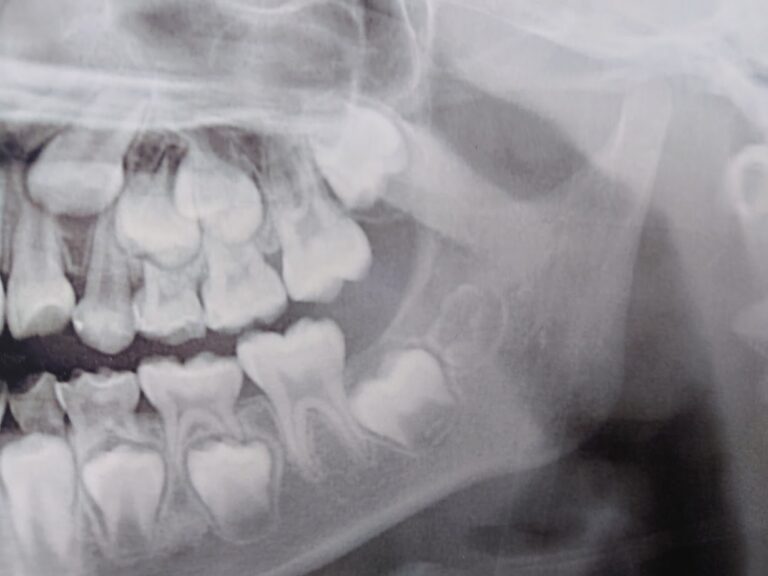

顎の成長や歯の生え変わりを利用して、将来的な本格矯正をより効果的に、あるいは不要にするための土台作りを行います。通常、数ヶ月から数年単位で、定期的なチェックと装置の調整をしながら進めます。

また、耳鼻疾患や悪習癖も不正咬合の原因の一つとなりますので、成長期に治していく必要があります。さらに、乱食い歯(歯列の凸凹・叢生)が予想される場合は歯列の拡大を成長期に行う必要があることがあります。

骨格に問題(あごが小さかったり大きかったり)のある方には成長のコントロールを行います。たいていの場合は、在宅時に使用する装置となります。歯を支える土台の骨が小さい場合は歯ぐきの骨(歯槽骨)を広げる装置などが入ります。口腔筋機能療法(MFT)を必要に応じて行います。

矯正治療に必要な各種検査を行います

必要に応じてレントゲン撮影、歯型取り、写真撮影、CT撮影などを行います。所要時間は1時間程度です。

乳歯が萌えかわり、身長の伸びのピークを迎えたら、第一期治療の評価を行います。その後、第一期治療で終了する子と、第二期治療に移行する子に分かれます。